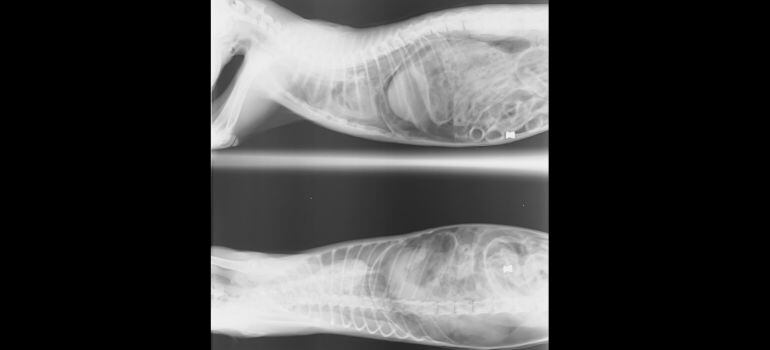

La clínica veterinaria confirmaron que su muerte había sido causada por el disparo de un balín.